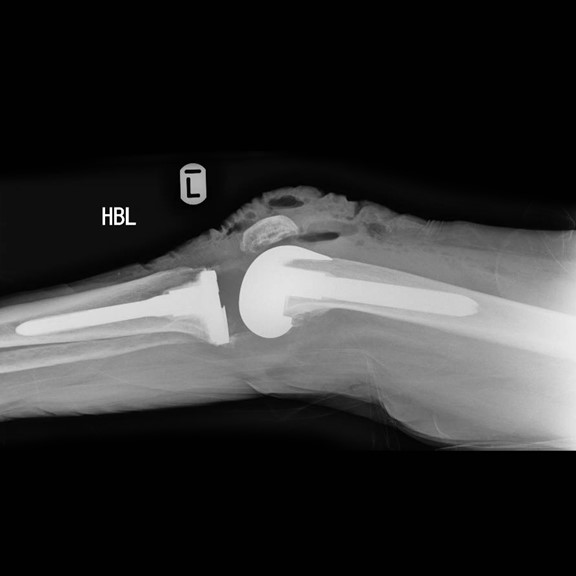

Generally, bone cement is used to fix a total knee replacement to the bone, in some cases where an uncemented knee replacement is used the host bone grows onto the implant. If this interface between the bone and the cement or the bone and the implant (in an uncemented knee) fails then the implant will loosen and will result in progressive pain. Usually loosening occurs many years after surgery, if it occurs early on it is often due to a technical problem during the implantation surgery.

Another cause of loosening can be a wearing out of the plastic insert that sits between the metal implants of the femur and tibia. These wear particles that are generated can cause quite extensive bone loss around the implant and this significantly increases the complexity of the surgery.

It is therefore important that your surgeon has a range of options available to him to reconstruct the knee after a failed knee replacement. This may include advanced surgical approaches, use of complex revision implants including custom made implants, use of bone graft or trabecular metal implants to reconstitute lost bone.